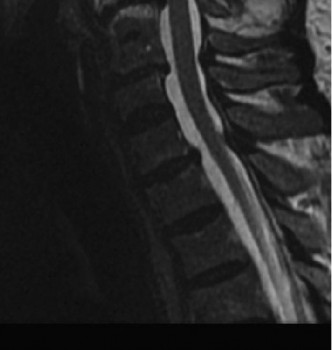

- MRI: The gold standard to assess spinal cord pathology (edema, hemorrhage, compression, contusion) and evaluate soft tissue compressive lesions (disc herniation, ligamentum flavum hypertrophy). Crucially, it delineates the extent and location of cord compression.

- CT Scan: Provides detailed bony anatomy, identifies fractures, osteophytes, and can assess spinal canal dimensions. CT angiogram may be considered if vertebral artery injury is suspected, particularly in fracture-dislocations.

- MRI Findings: The presence and extent of intramedullary hemorrhage (suggesting more severe cord damage) on MRI is a negative prognostic indicator, while pure edema is associated with better outcomes. The degree of spinal cord compression is also crucial.